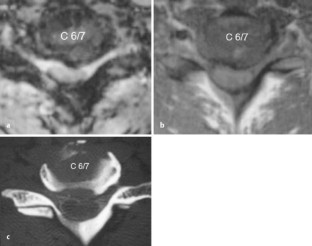

Disc herniation could be depicted in CTM as well as in MRI. The extent of herniation did not differ between CTM and T1w. The extent of herniation seemed higher on T2w than on T1w (p <0.001). Foraminal encroachment was easier to diagnose in CTM. When regarding transverse T1w and T2w images simultaneously, a missing root in MRI corresponded to a missing root in CTM and conventional myelography and vice versa. Our data demonstrated the relative inability of MRI to determine whether the compression is by soft tissue or bony structures.

Abb. 4a-c